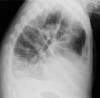

Atelectasia lóbulo medio.